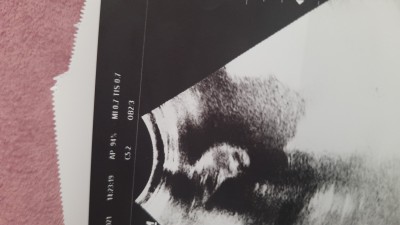

33+0 haftalığız doktorum ultrason görüntüsü verdi ama anlamadim bakarmisiniz

Gebelik haftası 33+0

Canım genellikle son haftalarda suyun yada bel kemiğinin görüntüsünü veriyorlar bir sıkıntı olursa bakmak için